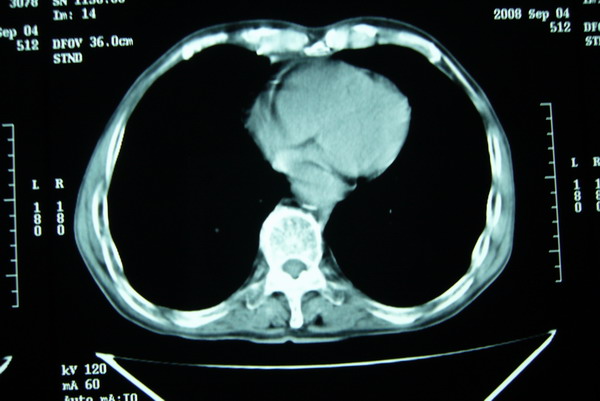

标题: CT15579:男 86岁 咳嗽 咳少量白痰 发热2天 吸烟史60年 [打印本页]

标题: CT15579:男 86岁 咳嗽 咳少量白痰 发热2天 吸烟史60年

右肺上叶巨大软组织肿块,轮廓不规则,纵隔内有肿大淋巴结,首先考虑肺癌。

右上肺一不规则团块,边缘有分叶和毛刺,纵隔有淋巴结肿大。右肺周围性肺癌首先考虑。